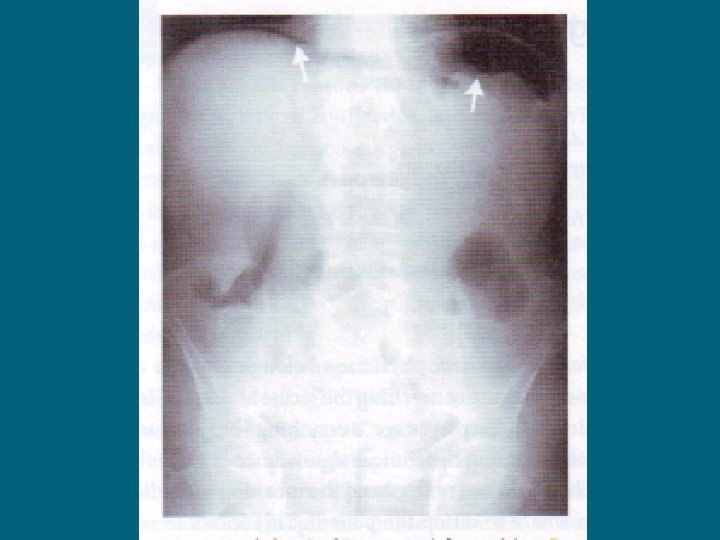

ILEO MECCANICO: DIAGNOSI RX DIRETTA ADDOME IN ORTOSTATISMO: presenza di livelli idroaerei

ILEO MECCANICO: DIAGNOSI ESAME OBIETTIVO: ISPEZIONE: Distensione addominale Ricerca di ernie Ricerca di cicatrici laparotomiche

ILEO MECCANICO: DIAGNOSI ESAME OBIETTIVO: PALPAZIONE: Dolorabilità Anse distese Ricerca di masse (volvolo? tumore? ) (Manovra di Blumberg)

ILEO MECCANICO: DIAGNOSI ESAME OBIETTIVO: PERCUSSIONE: guazzamento